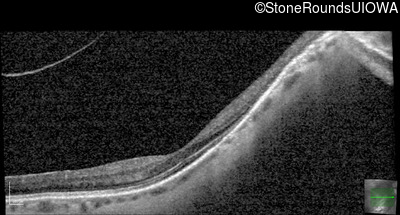

Optical Coherence Tomography - Left - 20/25 -2

Exemplar / OCT Stack